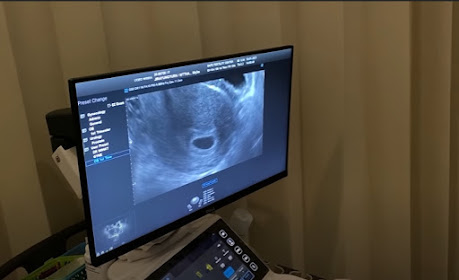

ដោយតារាស្រីនាង Mew និងស្វាមីអ្នកជំនួញលោក Saint បានរៀបការសាងជីវិតគ្រួសាររួមគ្នាបានមួយឆ្នាំជាងហើយ។ ទាំងគូក៏តែងនិយាយពីរឿងចង់បានកូនមករហូតផងដែរ ព្រោះអ្នកទាំងពីរសុទ្ធតែស្រលាញ់ក្មេងនិងព្រមធ្វើជាឪពុកម្ដាយគេហើយ។ ថែមតារាស្រីនាង Mew ក៏ធ្លាប់បាននិយាយក្នុងកិច្ចសម្ភាសន៍ផងដែរថារូបនាង បានសម្រេចចិត្តទុកពេលទំនេរមិនទទួលការសម្ដែងក្នុងមួយរយះនេះព្រោះកំពុងមានគម្រោងចង់បានកូន។ ពេលនេះក្ដីបំណងបានសម្រេច គូស្វាមីថ្មីថ្មោងផ្អែមល្ហែមមួយគូនេះបានប្រកាសដំណឹងមានកូនហើយ ព្រមទាំងបង្ហាញរូបភាពទៅឆ្លុះមើលក្នុងមុខសប្បាយរីករាយផងដែរ។